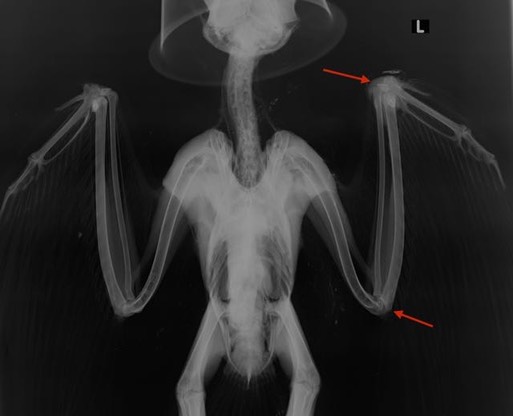

Great Horned Owl 17-624

We’re not sure what this Great Horned Owl crashed into, but it must have happened at least a week before she was found by hunters. She has an old wound on her left wrist. The prognosis for a fully functional wing is probably not very good, but she currently has pretty good extension in the wrist. We will see what happens.